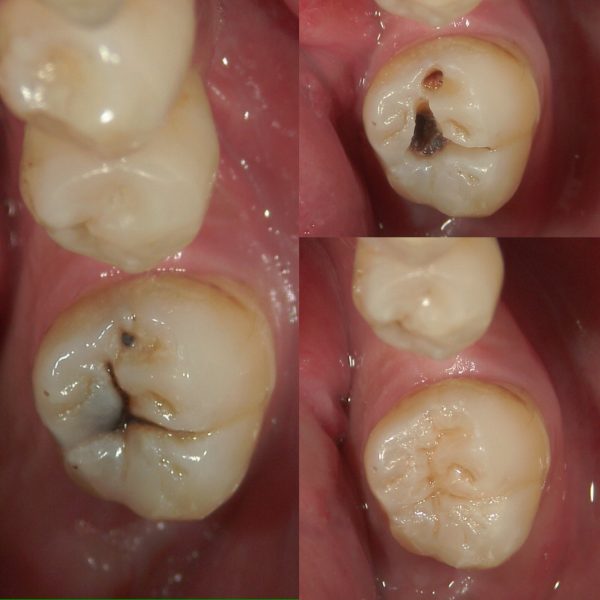

新年初仕事 奥歯のむし歯治療

むし歯を取り除きラバーダム下にてEDTA処理を行った後、強化コンポジットレジンにて充填を行います。歯の形態には意味があります。ダイレクトボンディングでは極力歯の形を再現することができるよう努めています。保険で用いられるCR治療との違いはラバーダムを行い強い接着を行うこと、材質が優れていることから変色や摩耗、咬耗しずらくむし歯再発もしにくい完成となります。ただ、奥歯で用いるとセラミックスに比べすり減りが起きやすく、また、欠けないとは言い切れないため再治療が必要になる場合があります。